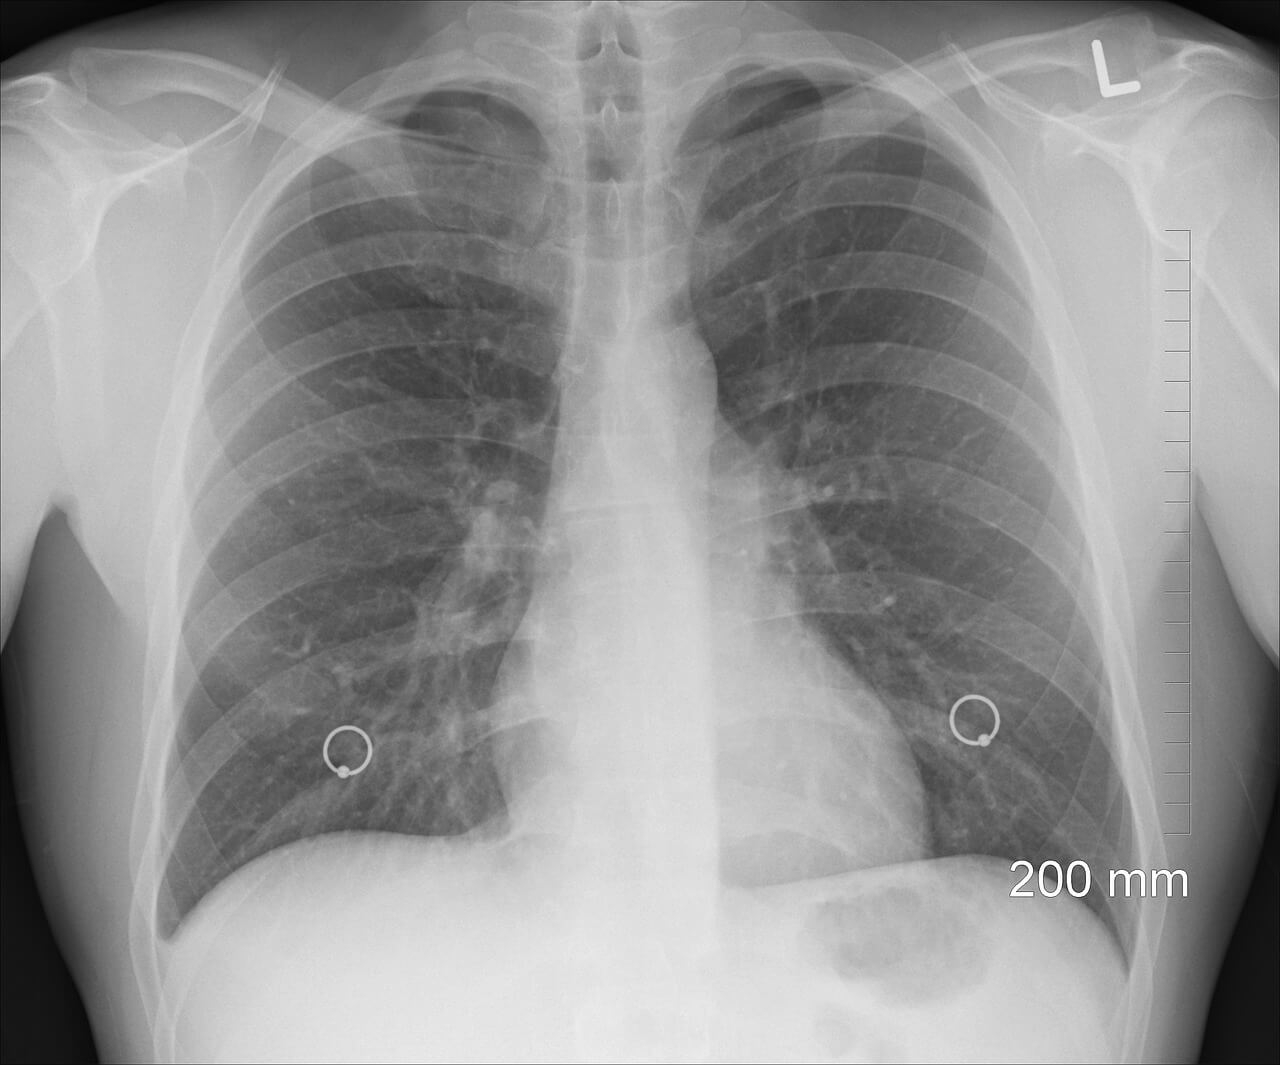

Il medico potrà consigliare anche altri esami, come:

- Radiografia al torace, utile per valutare lo stato di salute dei polmoni

- TC: scansione di tomografia computerizzata, che permette di osservare lo stato di salute della pleura

- ECG: l’elettrocardiogramma permette di valutare le condizioni del cuore, in modo da escludere la possibilità che il dolore al petto sia dovuto a problemi cardiaci.